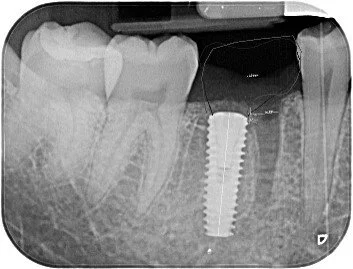

At his implant surgery appointment with Dr Dilan, the tooth was divided and precisely drilled through to create a channel for where the implant would be placed & an xray taken to confirm the angle at which the implant would be placed. After verifying the position, began the delicate process of surgically extracting the remaining tooth roots with extreme care to ensure as much of the bone between the roots is preserved to retain the implant.

3. Once the roots were fully removed, the titanium implant was placed and gently screwed securely into the preserved area of bone. Stitches were placed to pull the tissues together and a final xray confirming correct positioning of the implant taken. The appointment was completed within a 1hr 30min time span and the patient was happy to have both the painful tooth removed and his implant placed.